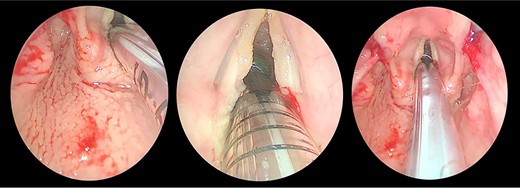

Transnasal flexible endoscope showing broad-based lesion affecting the middle two-third of the right vocal fold with a granular appearance of the interarytenoid region.

The patient maintained good oxygen saturation levels in room air with no signs of respiratory distress. She had a hoarse voice with a maximum phonation time of 10 s. Neck examination was unremarkable. Bedside transnasal flexible endoscope revealed bilateral vocal folds movement with polypoid lesions involving the middle two-thirds of the right vocal fold and the posterior part of the left vocal fold with edematous interarytenoid mucosa. Moreover, polypoid lesions were also seen in the base of tongue, epiglottis, with cobblestoning of the posterior pharyngeal wall (Figs 1 and 2). Basic laboratory tests were within the normal range. A contrasted neck computed tomography (CT) scan revealed bilateral asymmetric thickening of the vocal folds with medialization of the right vocal fold, with no enlarged cervical lymph nodes (Fig. 3).

Direct laryngobronchoscopy showing a polypoidal lesion on the middle third of the left vocal fold with a granular appearance of the interarytenoid region and cobblestoning of the posterior pharyngeal wall.

The patient underwent direct microlaryngoscopy (MLS) with multiple biopsies under general anesthesia. MLS revealed the same previous findings with a clear subglottic area (Figs 1 and 2). Multiple biopsies were obtained from the mentioned regions using punch forceps. There were no intraoperative or postoperative complications. The patient was discharged in stable condition the following day.